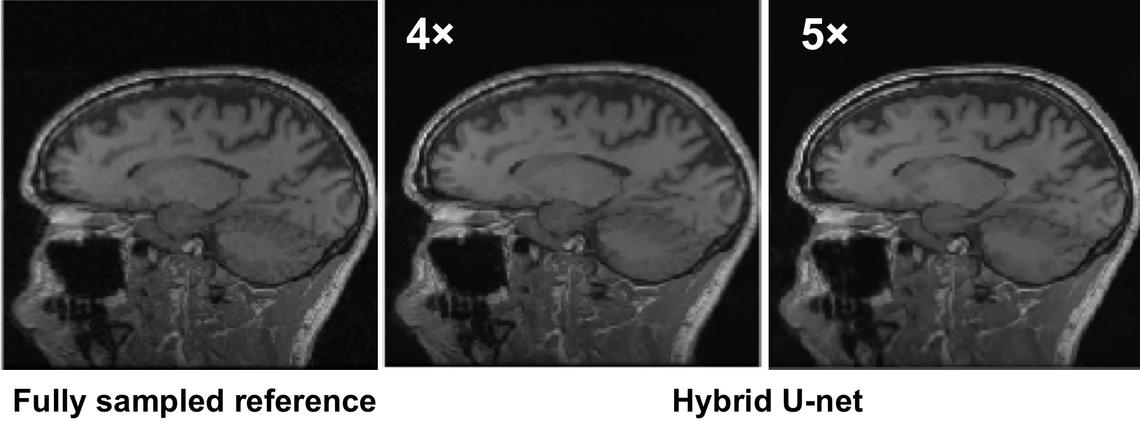

Example of deep-learning reconstructed images from undersampled data (R=4 and 5) versus the fully sampled reference image.

This research investigates the application of deep learning networks for reconstruction of undersampled MR datasets.

Since 2018, we have been exploring the application of deep-learning based methods for MR image reconstruction and introduced the pioneering hybrid-domain W-net concept.